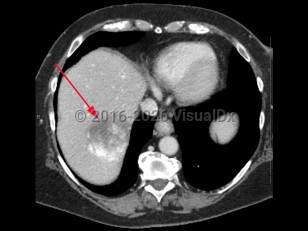

Imaging Studies image of Hepatic hemangioma - imageId=8340259. Click to open in gallery.  caption: '<span>Contrast enhanced axial CT scan of the abdomen demonstrates a mass in the right lobe of the liver with peripheral enhancement, consistent with hepatic hemangioma.</span>'

Contrast enhanced axial CT scan of the abdomen demonstrates a mass in the right lobe of the liver with peripheral enhancement, consistent with hepatic hemangioma.